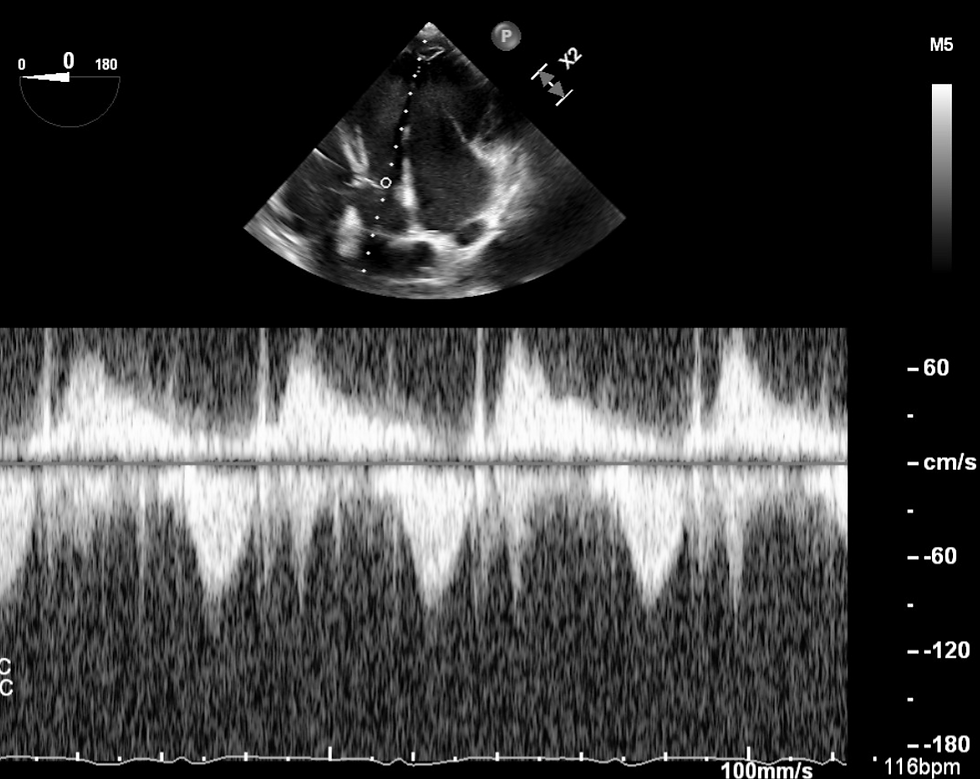

Pulse Wave and Continuous Wave Echo Doppler of Aortic Valve and LVOT- Deep Transgastric (TEE)